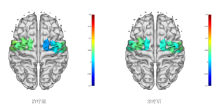

Comparison of HbO₂ levels in different ROIs between two groups pre- and post-treatment 单位:mmol/(L⋅mm)"

ROI | 组别 | n | 测试 | t值 | P值 | |

---|---|---|---|---|---|---|

PMC/SMA | 对照组 | 20 | 前测 | 0.013±0.023 | -0.599 | 0.564 |

后测 | 0.016±0.015 | |||||

BCI组 | 20 | 前测 | 0.023±0.032 | -3.965 | 0.003 | |

后测 | 0.051±0.027 | |||||

治疗前两组均值差 | -0.010±0.012 | -0.777 | 0.447 | |||

治疗后两组均值差 | -0.035±0.010 | -3.630 | 0.002 | |||

PSC | 对照组 | 20 | 前测 | 0.025±0.024 | -0.647 | 0.534 |

后测 | 0.032±0.030 | |||||

BCI组 | 20 | 前测 | 0.051±0.048 | 1.196 | 0.259 | |

后测 | 0.027±0.053 | |||||

治疗前两组均值差 | -0.026±0.017 | -1.529 | 0.143 | |||

治疗后两组均值差 | 0.004±0.019 | 0.229 | 0.821 | |||

M1 | 对照组 | 20 | 前测 | 0.036±0.032 | 1.162 | 0.275 |

后测 | 0.019±0.026 | |||||

BCI组 | 20 | 前测 | 0.048±0.025 | 1.108 | 0.294 | |

后测 | 0.032±0.050 | |||||

治疗前两组均值差 | -0.012±0.013 | -0.974 | 0.342 | |||

治疗后两组均值差 | -0.013±0.018 | -0.725 | 0.478 |